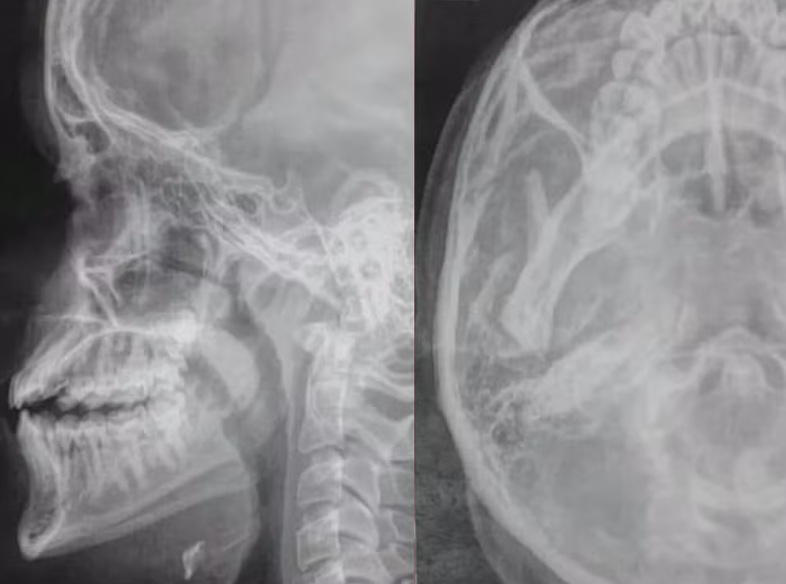

Em seguida, ao procurar por ajuda na direção da escola, ele foi derrubado no chão e passou a ser agredido com socos no rosto. Exames de raio-x mostraram como ficou o rosto da vítima após o ataque (veja acima).